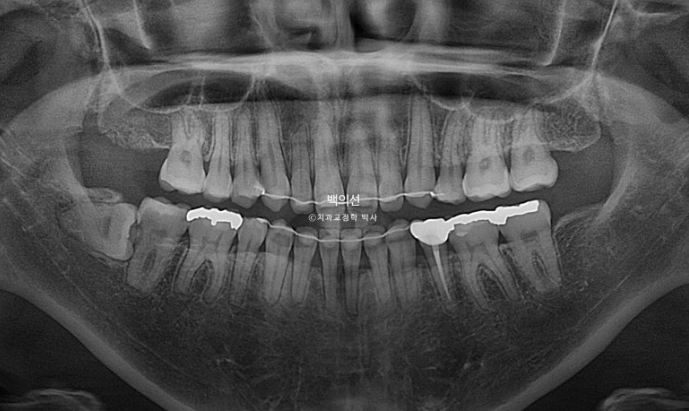

2년간의 교정기간동안 앞니 일부에 경미한 치근흡수가 보입니다.

치근평행도는 좋습니다.

위 앞니 기준 뒤로 4mm 들어갔고, 거미스마일 개선을 위해 위로도 2mm 올라간 것이 확인이 됩니다.

사실 앞니의 변화보다 주목해야할 것은?

아래턱의 위치입니다.

상악 전체치열 함입으로 인해 아래턱이 더 다물어지는 자가 회전이 일어나고 턱끝이 위로, 앞으로 약 2mm 이동했습니다.

하관이 짧아지고 턱끝이 실제로 앞으로 나오게 된 것입니다.

이렇게 실제로 턱끝이 앞으로 나온데다가 돌출입 개선으로 턱끝부위 근육긴장이 풀리며 호두턱이 사라져 아래턱 라인이 드라마틱하게 바뀌었습니다.